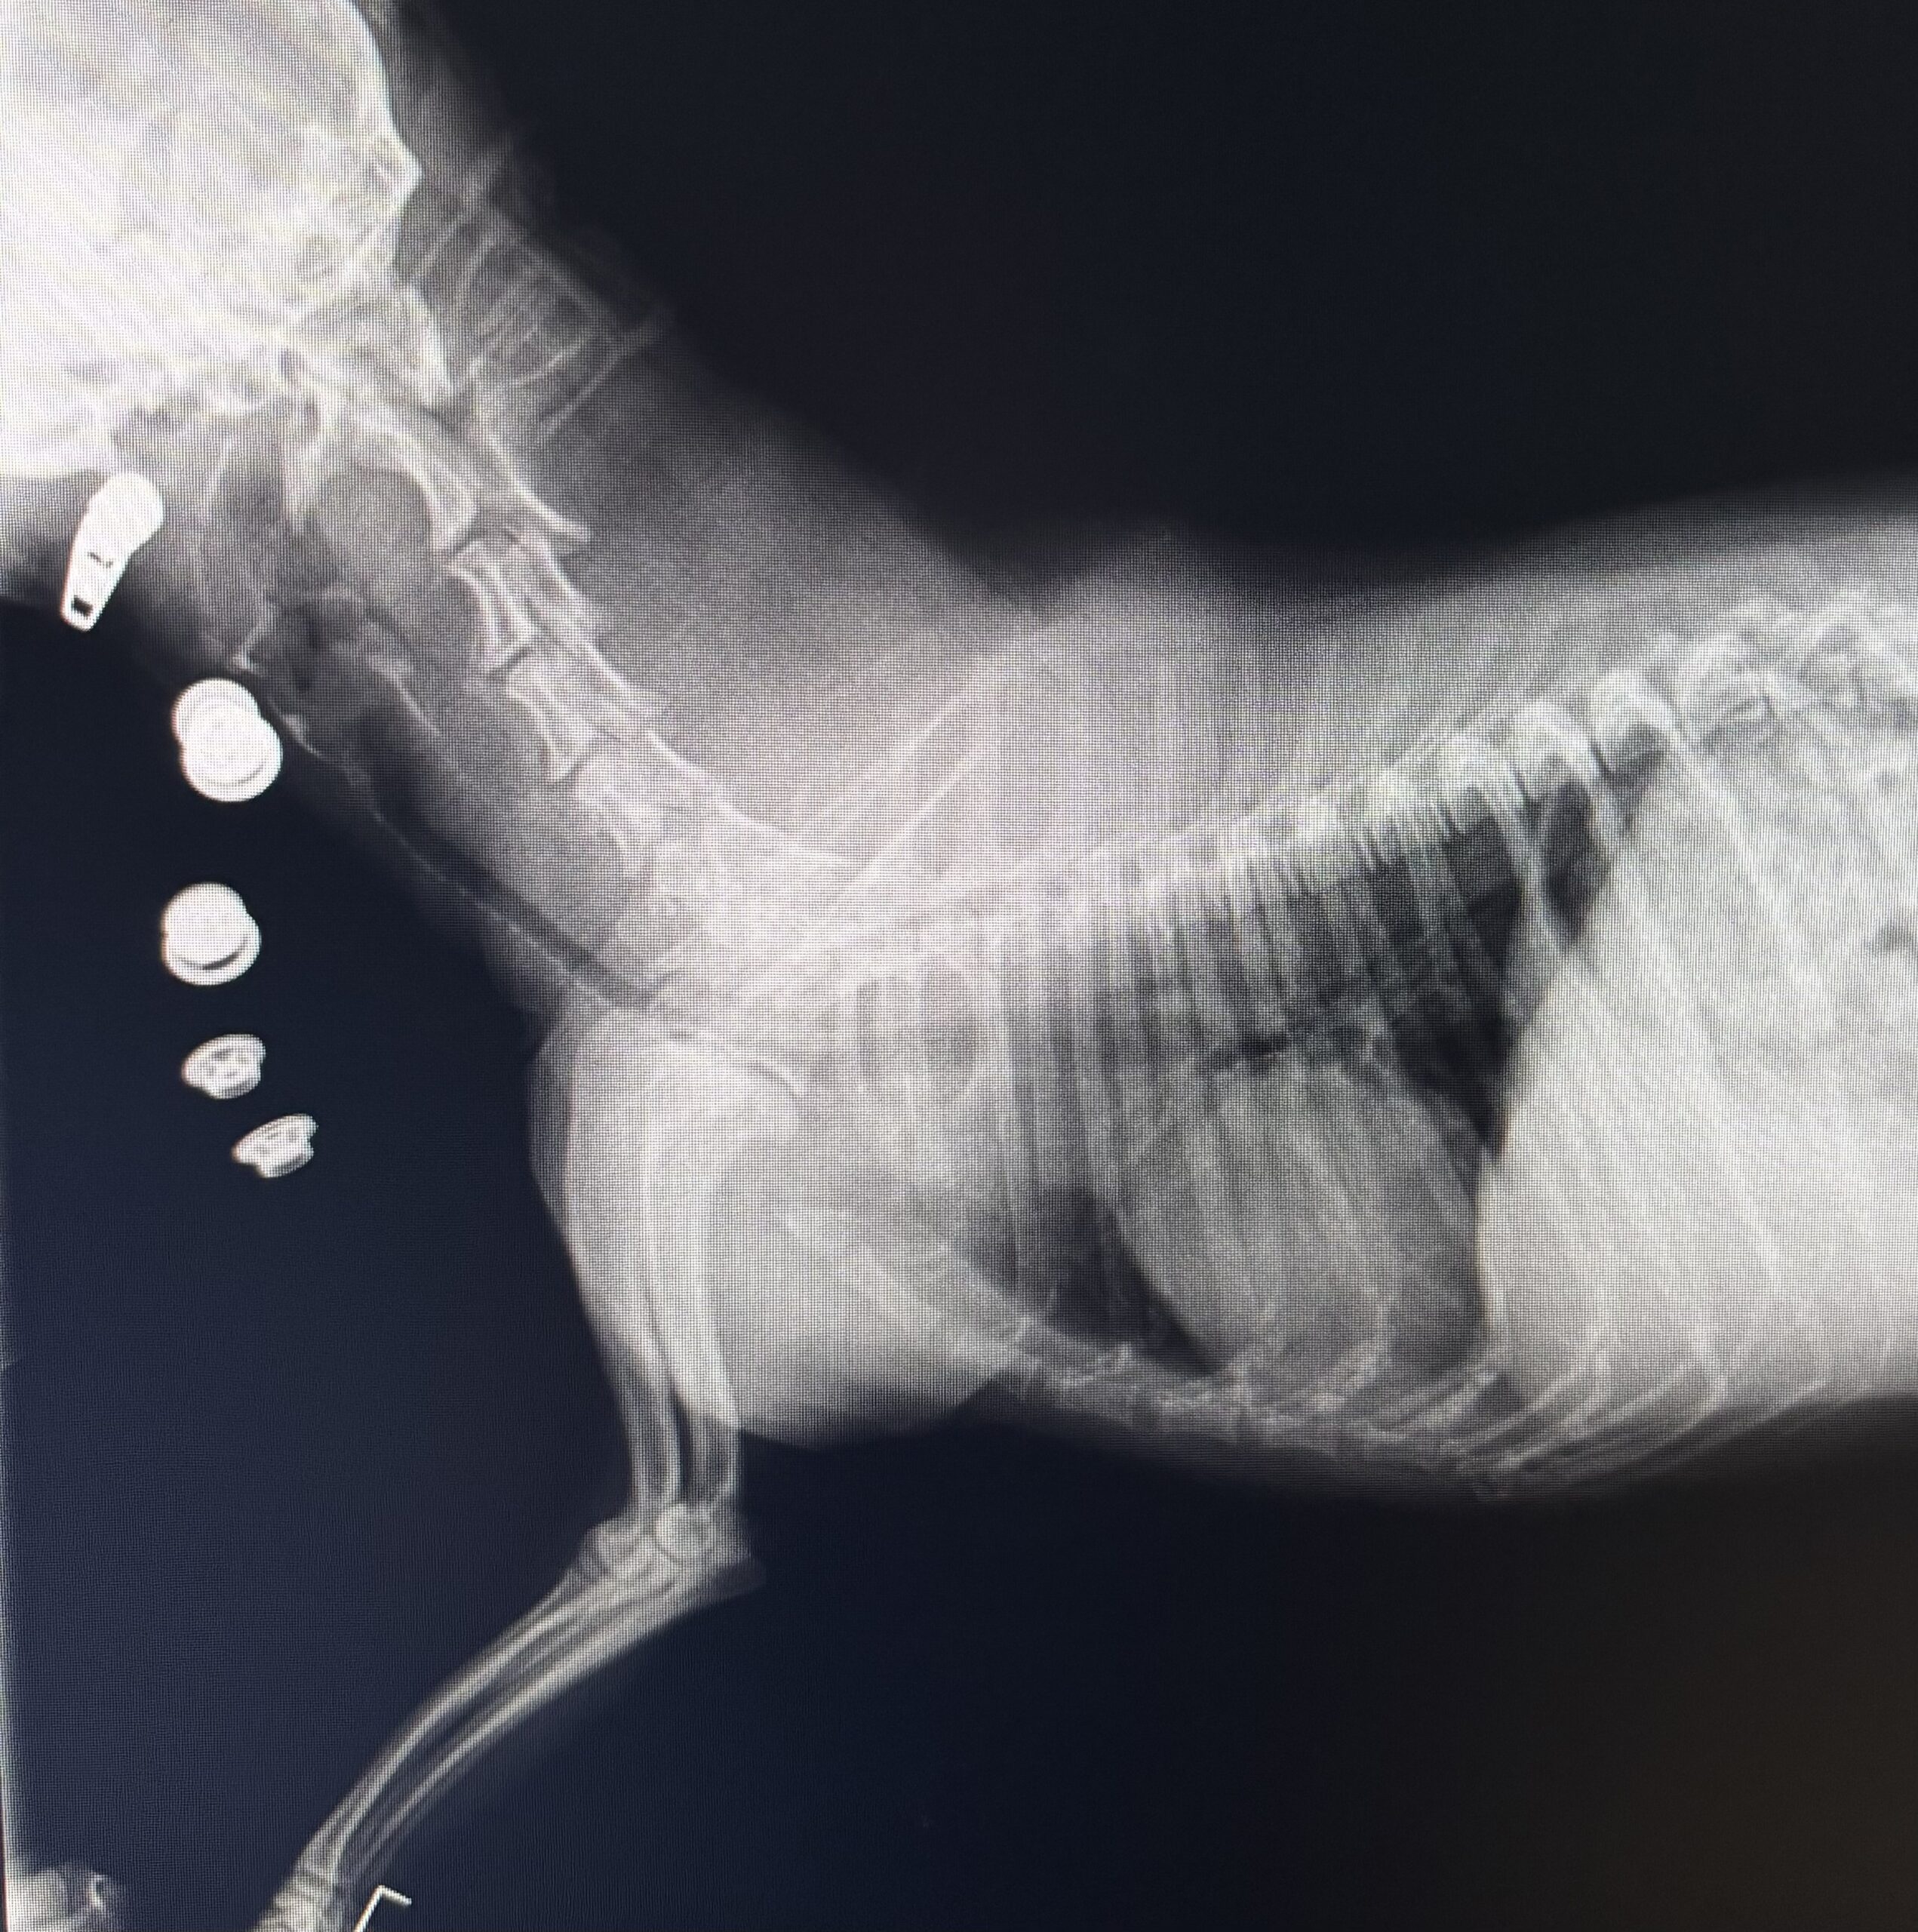

椎間板ヘルニア犬の致命傷:シンク内での「二本足姿勢による軸圧」

ダックスフンドなど軟骨異栄養犬種(椎間板が若くして変性・硬化する犬種)にとって、トリミング時の「姿勢」は脊髄への直接的な脅威となります。

- メカニズム:犬の背骨(脊椎)は、四つ足で立つことで「吊り橋」のように重力を分散させています。しかし、シャンプー時にシンクの縁に前足をかけさせたり、お腹を洗うために前肢を持ち上げたりする「二本足姿勢(立ち上がり姿勢)」をとらせると、重力が背骨に対して縦方向の強烈な圧縮力(軸圧)としてかかります。

- ヘルニアの発生:滑るシンクの中で犬が踏ん張ったり、嫌がって腰をねじったりする力(トルク)が加わると、脆くなっていた椎間板の外枠(線維輪)がこの軸圧に耐えきれずに破綻します。中のゼリー状の組織(髄核)が脊柱管内に勢いよく飛び出し、全身の神経の束である脊髄を強烈に圧迫・挫滅させます。

- 重大な後遺症:後肢の完全麻痺、排尿障害、さらには「深部痛覚(骨を砕かれるような痛みを感じる神経)」の消失を引き起こし、緊急の脊髄減圧手術を行わなければ生涯車椅子生活となる危険性があります。